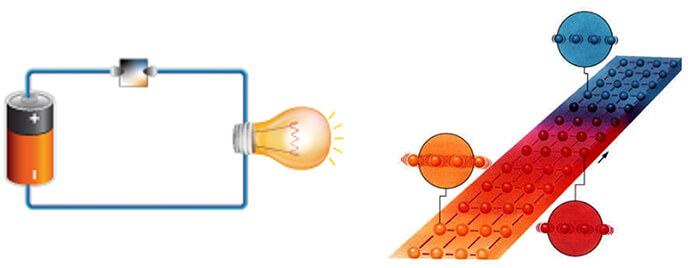

In 1820 after a long series of experiments, Ørsted discovered that a magnetized needle placed near a conductor moved when the wires were connected to a battery. At the time, the notions of electric circuit and current were unknown, but Ørsted suspected a link between electricity and magnetism. This experiment was the inspiration for the invention of coils to generate a magnetic field. If we turn the switch on, electrical current can flow through the coil and create a magnetic field.

In 1821, following the discovery of the phenomenon of electromagnetism by the Danish chemist Ørsted, Faraday built two machines to produce what he would call an electromagnetic rotation: the continuous circular movement of a magnetic force around a wire is the principle of an electric motor. In this experiment, if we rotate a magnetic field, shown here as a u-shaped magnet, it creates an electric current, to power a light bulb in our example.

This is still the way we generate electricity today. The magnet used is rotated as a result of the power created by the action of water such as with in hydroelectric power plants, with heat in conventional or nuclear power plants, with wind as in windmills or with mechanical effort, dynamo.